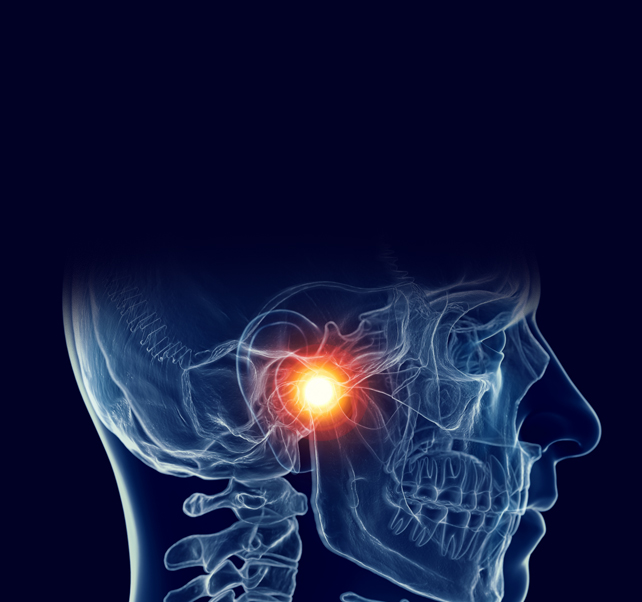

| 스플란트 | CR | 턱관절치료용 | 800,000 |

| Nightgard | 이갈이용 | 600,000 | |